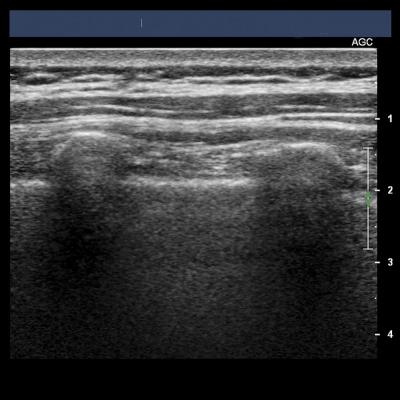

An ultrasound of the lungs could help doctors quickly determine if a pregnant woman with preeclampsia is at risk for respiratory failure, suggests preliminary research published in the April issue of Anesthesiology .

Pulmonary edema is typically caused by heart failure, but also can be caused by lung inflammation. Researchers analyzed the use of lung ultrasounds, which can assess lung edema, are easier to use than cardiac ultrasound and can be performed with devices commonly found in maternity wards. Lung ultrasound highlights white lines mimicking comet tails, irradiating from the border of the lungs. These lines are the reflection of water in the lungs. The detection of three or more lines strongly suggests the diagnosis of pulmonary edema.

Researchers performed both cardiac and lung ultrasounds before and after delivery in 20 women with severe preeclampsia. Five of the 20 women (25 percent) had pulmonary edema prior to delivery according to lung ultrasound, while four (20 percent) had the condition according to the cardiac ultrasound. The lung ultrasound identified a patient with non-cardiac pulmonary edema, which the cardiac ultrasound did not detect.